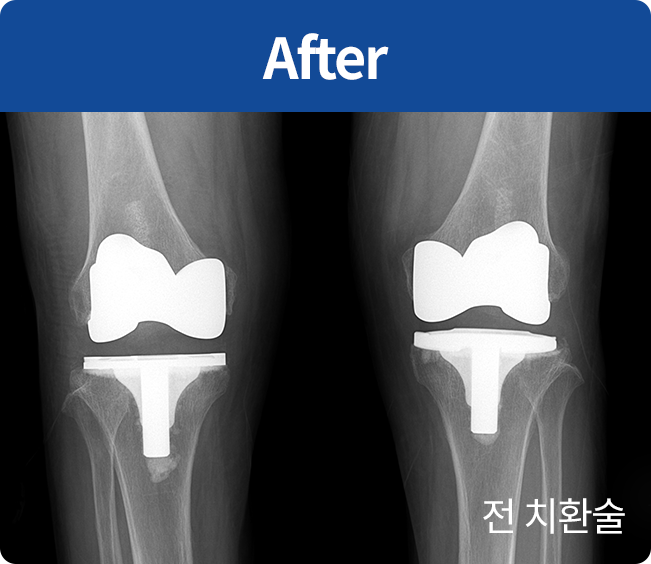

인공 관절 치환술

퇴행성관절염 및 기타 관절손상으로 통증이 심해

정상생활을 할 수 없고 다른 치료나 시술로 효과가 없는 경우에 시행하는 수술법(부분 치환술, 전 치환술)